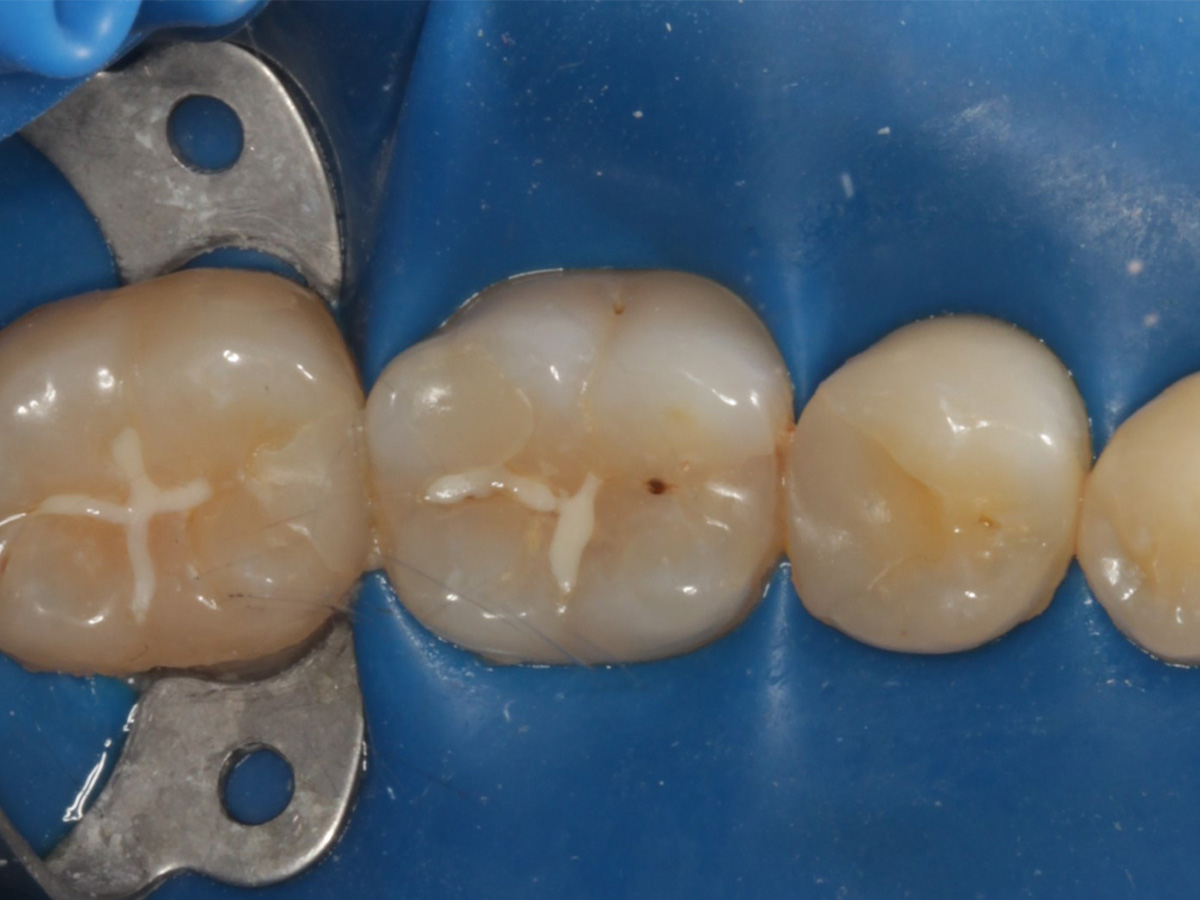

Kavitäten gefüllt (Injektion Moulding: Flowkomposit, erwärmtes Seitenzahnkomposit aus Karpule)

Abbildung 20

Abbildung 21

Zahnseidenkontrolle: kein Überschuss, satte Kontaktpunkte

Abbildung 22

Fertige Restauration Zahn 46